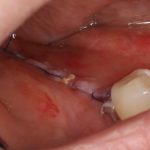

Послеоперационный период

Обычно, через день после операции рана выглядит вот таким образом:

Отёк, болезненные ощущения, затрудненное открывание рта — вполне себе обычная симптоматика после подобных операций. Впрочем, как и после остеопластик другими методами.